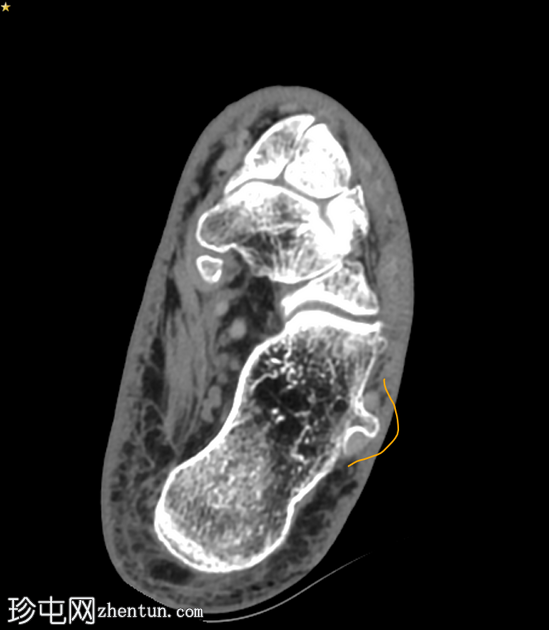

跟骨外侧

疼痛

。

年龄:65岁

性别:女

跟骨轴位CT

轴位

平扫

轴位骨窗